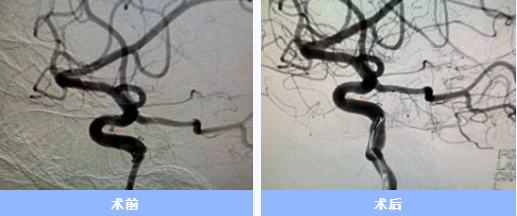

入院后急診完成了頭頸部血管檢查,卻未發(fā)現(xiàn)動(dòng)脈瘤。神經(jīng)內(nèi)科一病區(qū)負(fù)責(zé)人胡蘇華當(dāng)晚緊急為患者做了更精確的腦血管造影,終于發(fā)現(xiàn)右側(cè)頸內(nèi)動(dòng)脈上藏著一個(gè)極其微小的動(dòng)脈瘤——直徑僅約1毫米左右,堪稱(chēng)從醫(yī)二十多年來(lái)遇見(jiàn)的最難發(fā)現(xiàn)的"炸彈"。

手術(shù)當(dāng)天,胡蘇華與主治醫(yī)師陳浩協(xié)作,首先經(jīng)患者右手橈動(dòng)脈成功建立治療通道,隨后才實(shí)施全身麻醉,以最大限度縮短麻醉時(shí)間。憑借精湛技藝,團(tuán)隊(duì)迅速而完整地栓塞了動(dòng)脈瘤。術(shù)后患者很快在ICU蘇醒,四肢活動(dòng)良好,第二天即返回普通病房。